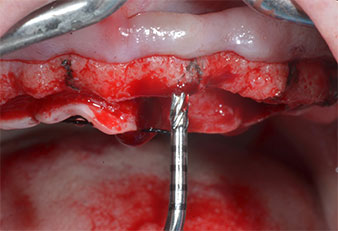

Wegen des relativ harten Knochens (D2) an den Positionen 11 und 21 wurden die 10 mm langen Implantatlager in diesem Bereich abschließend mit einem 4-mm-Spiralbohrer, dem chirurgischen Winkelstück WS-75 L von W&H und dem W&H Implantmed Implantologiemotor in Verbindung mit dem optionalen W&H Osstell ISQ module präpariert. Im Gegensatz dazu wurde der weiche Knochen der Implantatlager im Seitenzahnbereich mit dem Piezomed I3P auf den abschließenden Durchmesser von 3 mm erweitert. Die Implantate wurden dann transgingival eingesetzt, die Einheildauer betrug drei Monate (Abb. 6-10). Die vorhandene Prothese wurde auf vier provisorischen Implantaten abgestützt (Abb. 8).

Das gewählte kombinierte Präparationsverfahren, mit rotierender definitiver Präparation der anterioren Implantatlager in hartem Knochen erwies sich als effektiv, während die piezochirurgische Präparation für den posterioren weichen Knochen geringer Höhe optimal geeignet war.